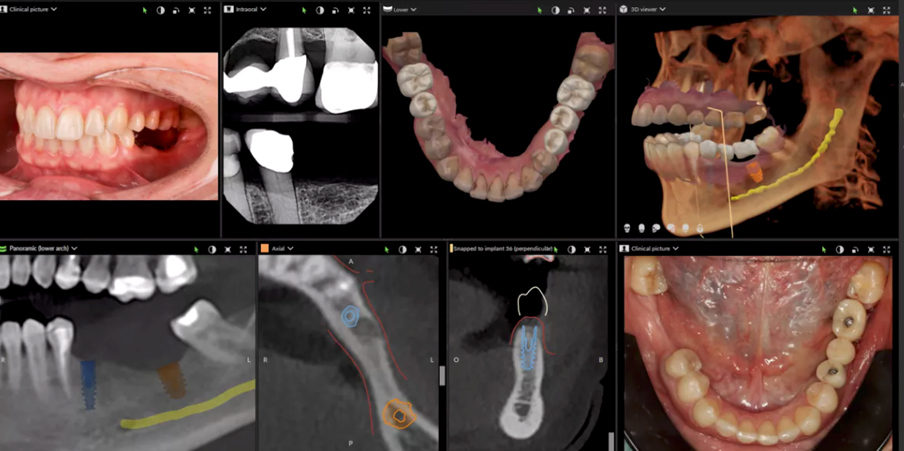

Phân tích hình ảnh CBCT 3D 🧠

Quy trình kỹ thuật số toàn diện: Hình chụp CBCT, lập kế hoạch đặt implant và phục hình răng trên implant – Ca lâm sàng thực tế cho sinh viên học Cấy ghép Nha khoa tại NTTU (Nguồn: dexis.com/en-us/dtx-studio-clinic-imaging-software).